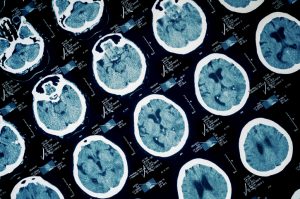

According to Alzheimer’s.org, many older people suffer a TBI because seniors are more likely to fall then other age groups. Developing Alzheimer’s is one of the risks of a serious TBI accident. The organization recommends that victims get immediate treatment. This includes getting a neurological assessment of their memory, ability to think, their hearing, vision, balance, touch, reflexes and anything that might affect their brain function. A computed tomography (CT) may be required.